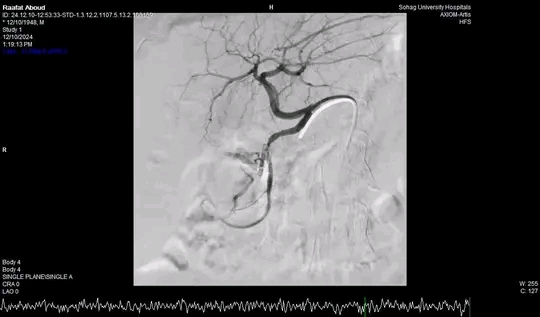

وأضاف الدكتور أحمد كمال المدير التنفيذي للمستشفيات الجامعية انه بعد اجراء الفحوصات للمريض تبين وجود قرحة كبيرة بالاثني عشر وشريان نازف، حيث نجح الفريق في التحكم المبدئي بالنزيف عن طريق تركيب مشبك معدني بالمنظار وحقن للقرحة النازفة، ثم تم استدعاء فريق أطباء وحدة الاشعة التداخلية علي الفور وتم عمل غلق للشريان النازف بشكل عاجل من خلال جهاز القسطرة.

وذكر الدكتور نايل عبد الحميد رئيس قسم امراض الباطنه ان هذا التدخل الطارئ لايقاف النزيف من خلال المنظار او من خلال غلق الشريان بواسطه الاشعة التداخلية جنب المريض من التعرض للحل الجراحي في هذا العمر، مشيراً الي ان المريض الآن في حالة مستقرة حيوياً وتوقف تام للنزيف وتحسن لوظائف الكلي والكبد وتم خروجه من وحدة الرعاية المتوسطة للمتابعة بالقسم الداخلي

وأوضح الدكتور محمد زاكي رئيس قسم الأشعة أن مثل هذه الحالات تعد من الطوارئ الطبية الخطيرة والتي تستوجب عمل قسطره شريانية عاجلة لغلق الشرايين النازفه مشيراً أن وحدة الأشعة التداخلية تم تزويدها بجهاز أشعه محوري متقدم لاجراء مثل هذه الحالات، وأن هذا النجاح هو نتيجة لتعاون أقسام المستشفي مع وحدة الأشعة التداخليه لتقديم خدمة مميزه للمرضي.